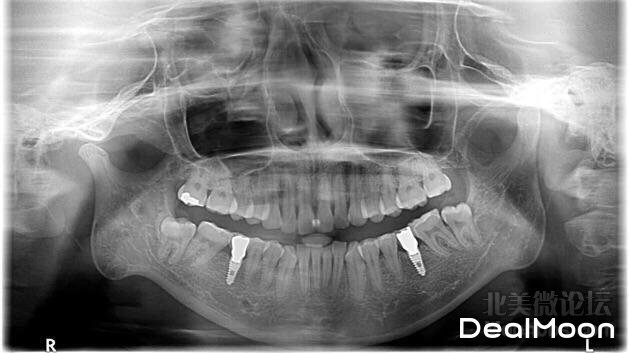

希望这张图不会吓到大家,这是我拔下边两颗智齿前拍的X光。那个两个异样的就是植得两颗牙齿。对于智齿来说,一定看医生要不要拔。我是等到长出来之后天天痛,才知道有智齿了,去看医生后,我的智齿离前边牙齿很近,时间久了会影响前边的牙齿,比如牙齿松动问题。最后一下两颗都拔出来了。你问我痛不痛,我会说手术中不同,甚至说我都不知道,因为是全麻的手术。但是等醒来之后,麻药劲过了,我的妈呀,疼了一天,而且也不能吃东西,只能吃流食。麻药劲也是一天才全下去,太强了。拔智齿之后一定要注意的是从医生那里要一个清理伤口的针管,有些医生不主动给。因为拔了智齿后后有个大洞,吃东西会近东西,这时候就需要这个东西用水冲出来,要不会感染,长时间不能愈合起来。整体来说现在我的牙齿已经很好了,医生说除了下边有几个牙齿不太整齐之外,不过完全看不出来。